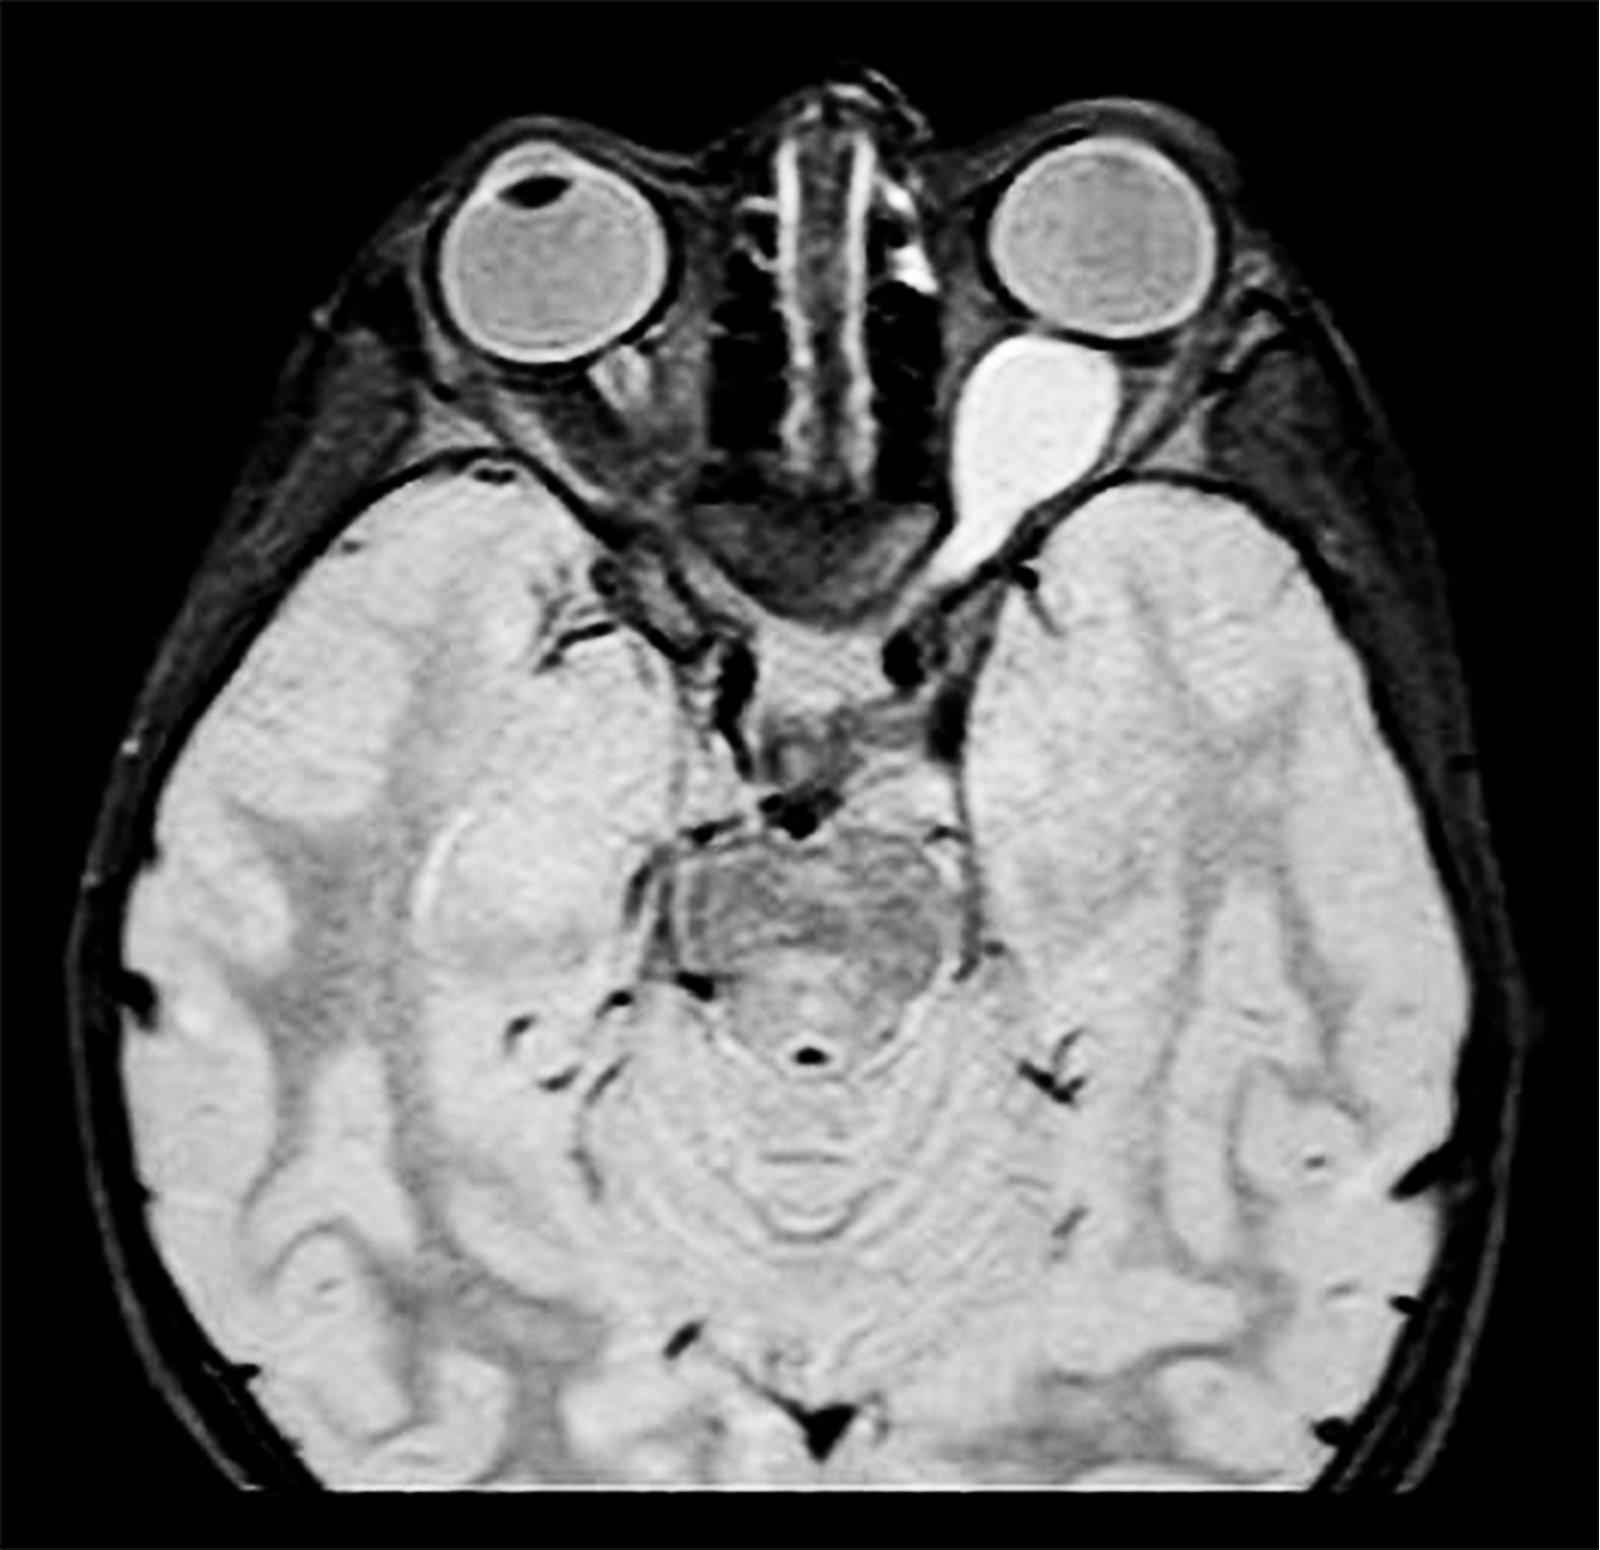

Axial MRI (T1-weighted) showing fusiform enlargement of the optic nerve–glioma characteristic of Neurofibromatosis Type 1 (NF1). The involved optic nerve appears thickened with a homogeneous signal pattern, producing the classic “pseudo–cerebriform” contour. The surrounding orbital fat planes are preserved, while the contralateral optic nerve maintains normal caliber. This imaging elegantly illustrates the hallmark benign, slow-growing nature of NF1-associated optic pathway gliomas, often presenting in childhood with insidious visual decline, proptosis, or strabismus. The bilateral symmetry of the globes contrasted against the distorted optic nerve architecture makes this a striking radiologic example.

High-resolution MRI Orbit Protocol using 1.5T Siemens Magnetom System with axial T1-weighted sequences